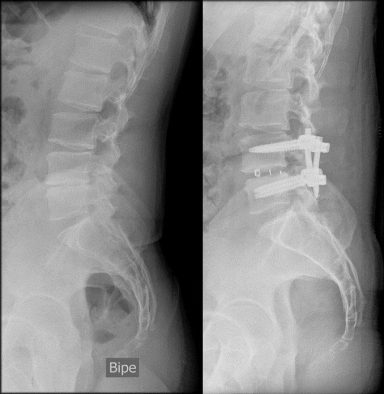

Las vértebras L4-L5, totalmente colapsadas, y apófisis transversas impactando en la cresta iliaca, dieron el resultado final de una cojera permanente, por lo que me realizan una artrodesis lumbar con OLIF.

Antes de la cirugía lumbar, conseguía correr con mi visible cojera y fuertemente medicado, en la categoría de Paratriatlón PTS5.

A día de hoy, utilizo silla de carrera y handbike.